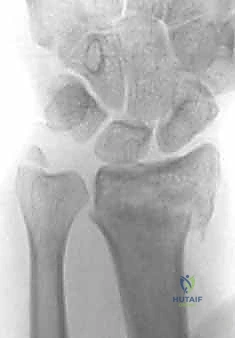

التشخيص الدقيق: خطوة أساسية قبل الجراحة

يعتمد الأستاذ الدكتور محمد هطيف في عيادته بصنعاء على منهجية تشخيصية صارمة تضمن اختيار العلاج الأمثل:

1. الفحص السريري: لتقييم الدورة الدموية، حركة الأصابع، وحالة الأعصاب.

2. الأشعة السينية (X-rays): وهي الفحص الأساسي لتأكيد الكسر، وتحديد مكانه، ومدى الإزاحة والتفتت.

3. الأشعة المقطعية (CT Scan): في الكسور المعقدة والممتدة داخل المفصل، يطلب الدكتور هطيف أشعة مقطعية ثلاثية الأبعاد لبناء تصور دقيق لسطح المفصل، مما يساعد في التخطيط الجراحي لوضع الشريحة الظهرية بدقة متناهية.